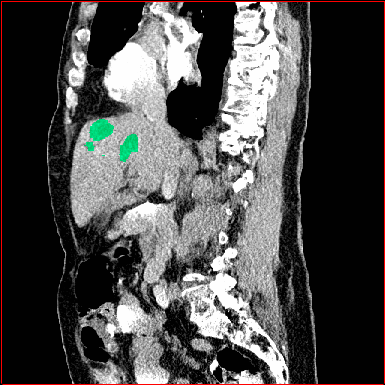

MAISI-v2 Controlnet qualitative Results:

Figure 5 shows qualitative results for MAISI-v2 Controlnet on 5 types of tumors.

Liver Tumor

0.75×0.75×0.50.75\times 0.75\times 0.5

mm

512×512×768512\times 512\times 768

Figure 5: MAISI-v2 segmentation-guided results for five types of tumors. We show results for different voxel spacing and volume size to demonstrate the flexibility of MAISI-v2. Different Hounsfield Unit window is used to better show the contrast between tumor and normal tissues.